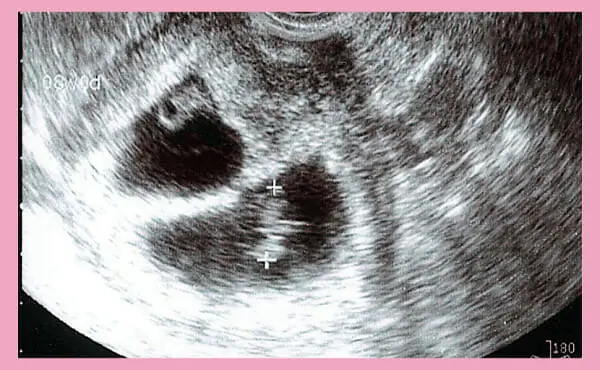

这个图片是双胞胎8周时的超声照片。